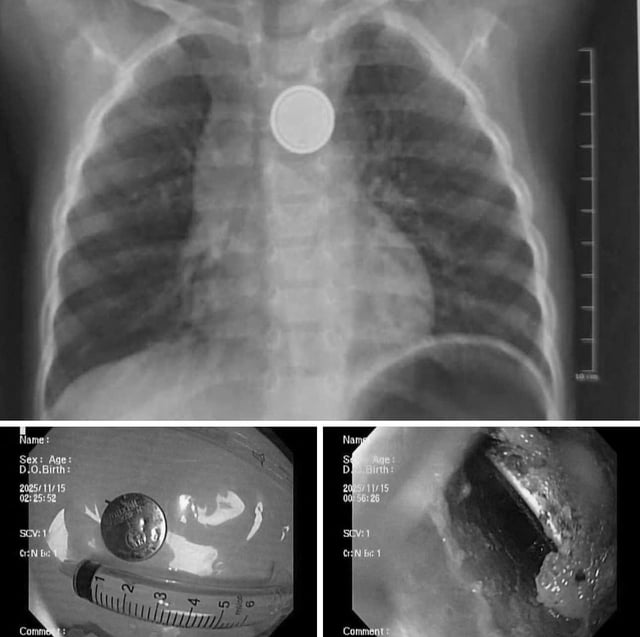

Imej objek asing, bateri butang, dalam esofagus kanak-kanak semasa X-ray dan endoskopi.

Di sini, doktor melakukan X-ray, keputusan menunjukkan objek asing tersangkut di esofagus.

Pasukan endoskopi kecemasan dengan cepat dan berjaya mengeluarkan bateri. Walaupun rawatan kecemasan awal, melalui pemerhatian langsung, pasukan endoskopi mencatatkan kawasan kakisan yang menyebabkan ulser esofagus.